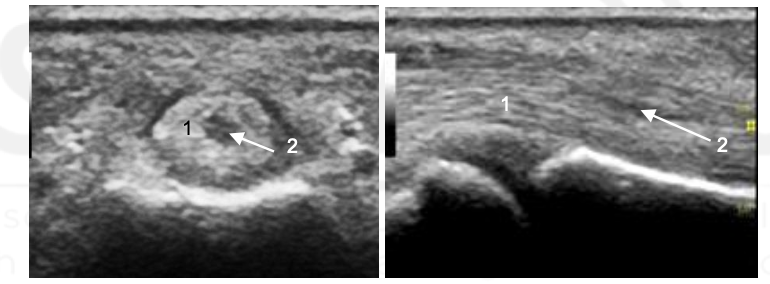

What are 1 and 2?

1 - Middle phalanx

Ganglionic Cyst

What is the arrow pointing to?